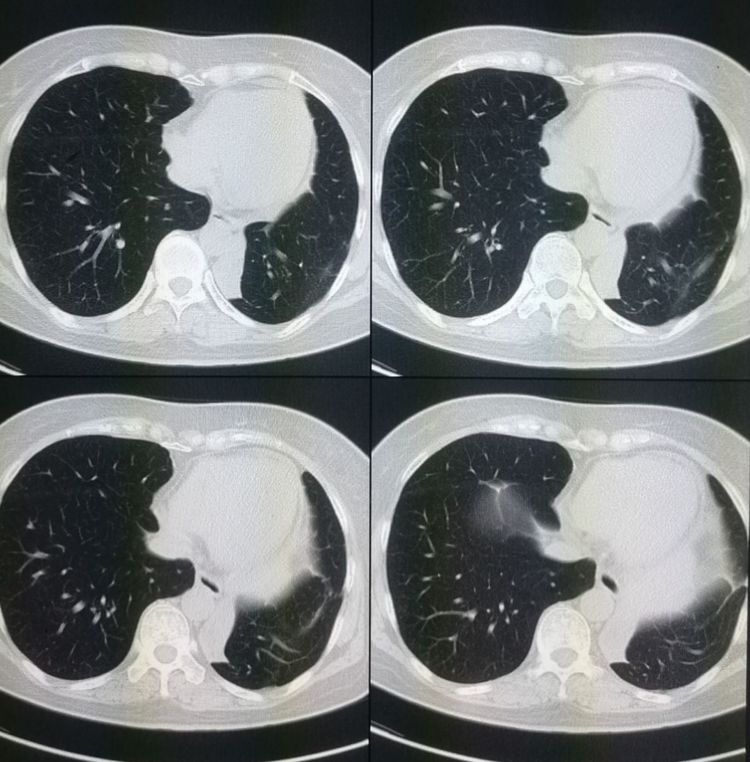

期间病情有反复,又做了放射性粒子植入,接近第4年的时候开始口服靶向药物,病情稳定!今年复查未见复发征象: